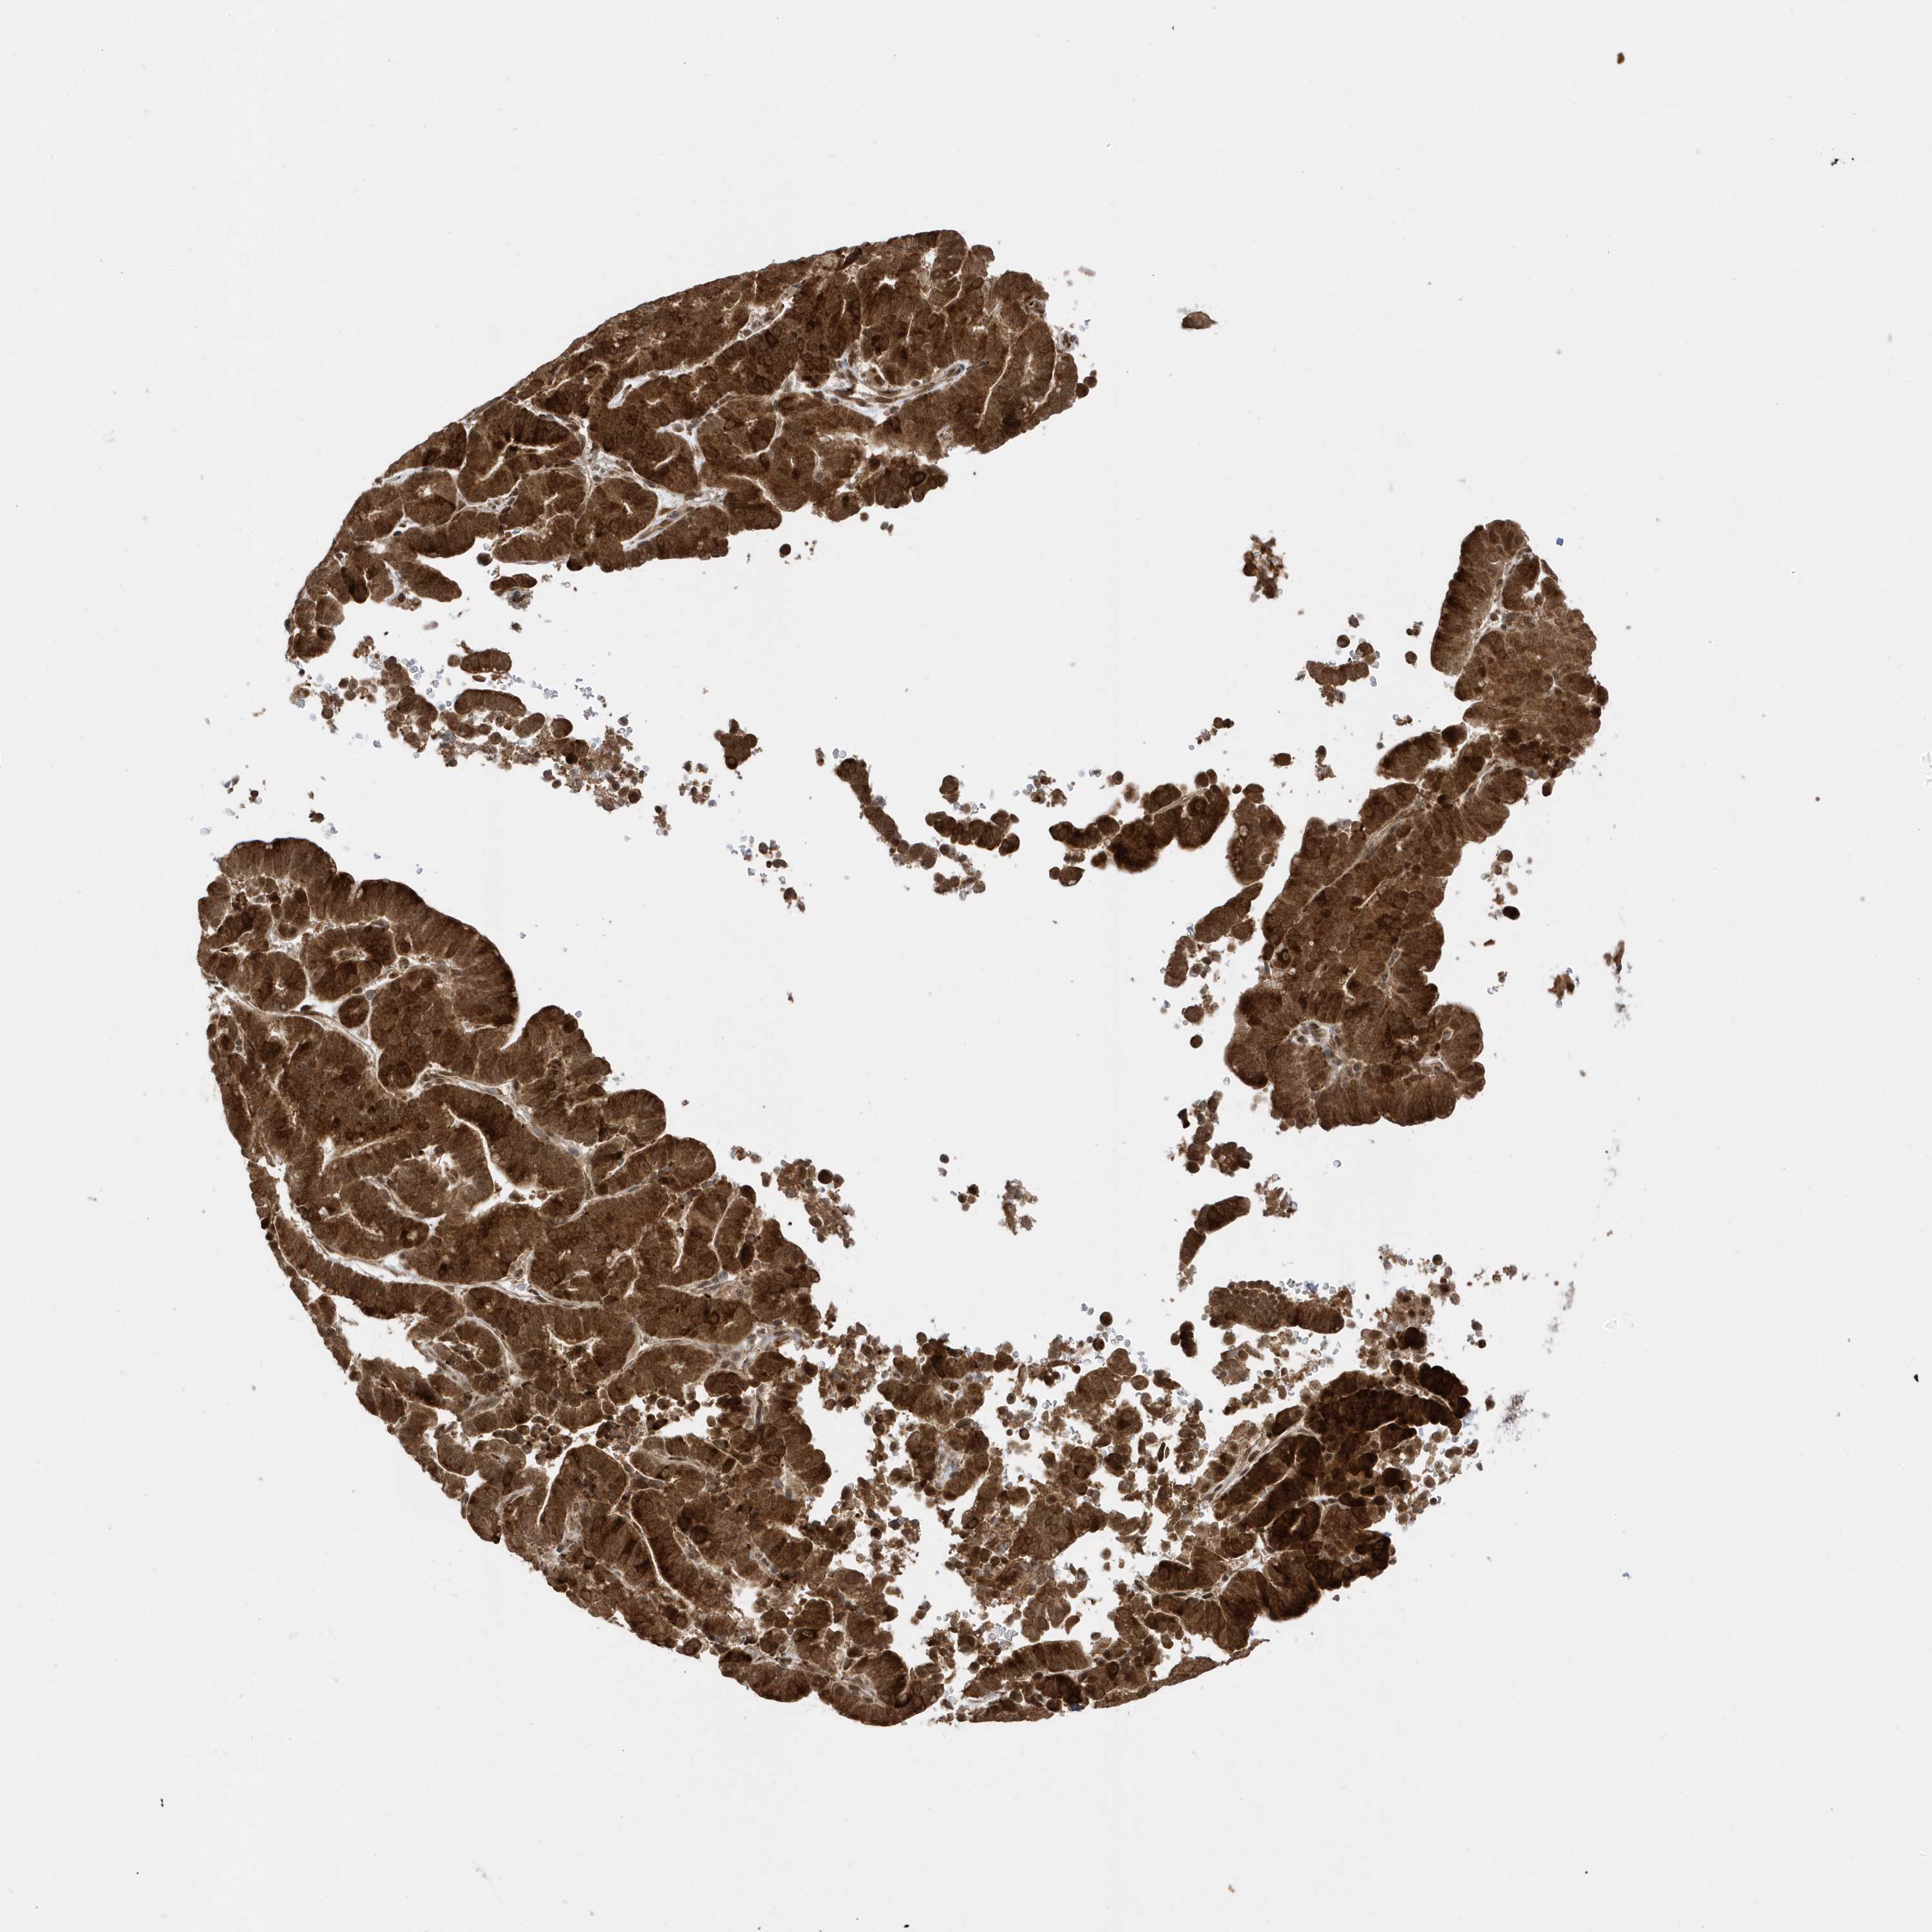

LIVER CANCER - Protein expressioni

A mouse-over function shows sample information and annotation data. Click on an image to view it in a full screen mode. Samples can be filtered based on level of antibody staining by selecting one or several of the following categories: high, medium, low and not detected. The assay and annotation is described here.

Note that samples used for immunohistochemistry by the Human Protein Atlas do not correspond to samples in the TCGA dataset.

Antibody stainingi

Antibody staining in the annotated cell types in the current human tissue is reported as not detected, low, medium, or high, based on conventional immunohistochemistry profiling in selected tissues. This score is based on the combination of the staining intensity and fraction of stained cells.

Each image is clickable and will lead to virtual microscopy that enables deeper exploration of all samples and also displays staining intensity scores, fraction scores and subcellular localization as well as patient and tissue information for each sample.

Antibody HPA034712

Staining

High

Medium

Low

Not detected

Intensity

Strong

Moderate

Weak

Negative

Quantity

>75%

75%-25%

<25%

None

Location

Nuclear

Cytoplasmic/membranous

Cytoplasmic/membranous,nuclear

Cholangiocarcinoma

Carcinoma, Hepatocellular, NOS